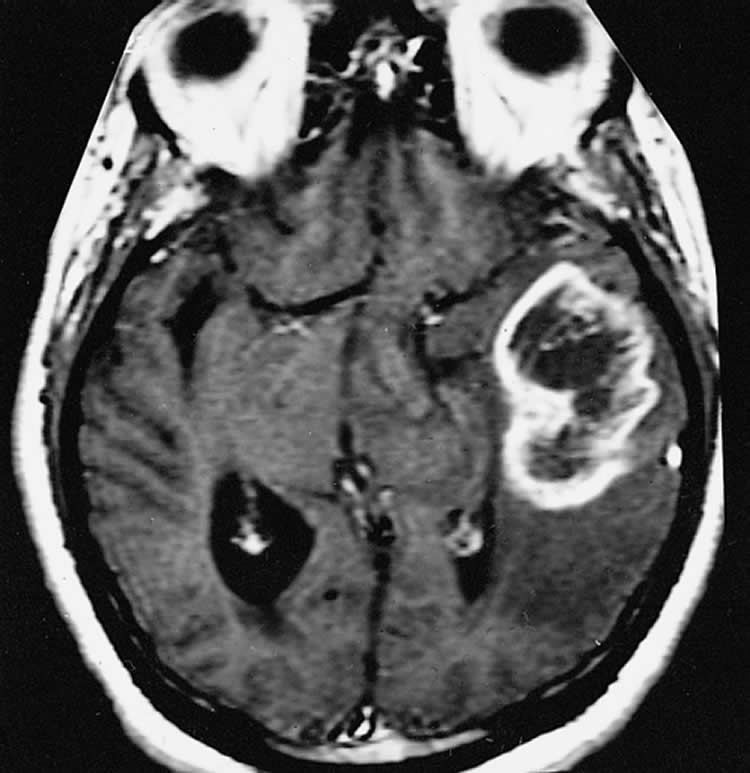

Image Source: The image is credited to The Armed Forces Institute of Pathology and is in the public domain